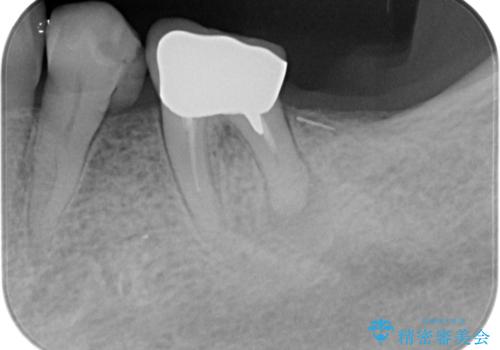

- 左下の大臼歯(6番)の根の治療を行いました。

左下6番の根管治療は六本木院の林院長にお願いしています。

- 根管治療により痛みや腫れがひかない事や、術後に痛みや腫れが生じる事、治療によるファイル破折やパーフォレーションなどの偶発症、術後の歯根破折を生じる可能性もあります